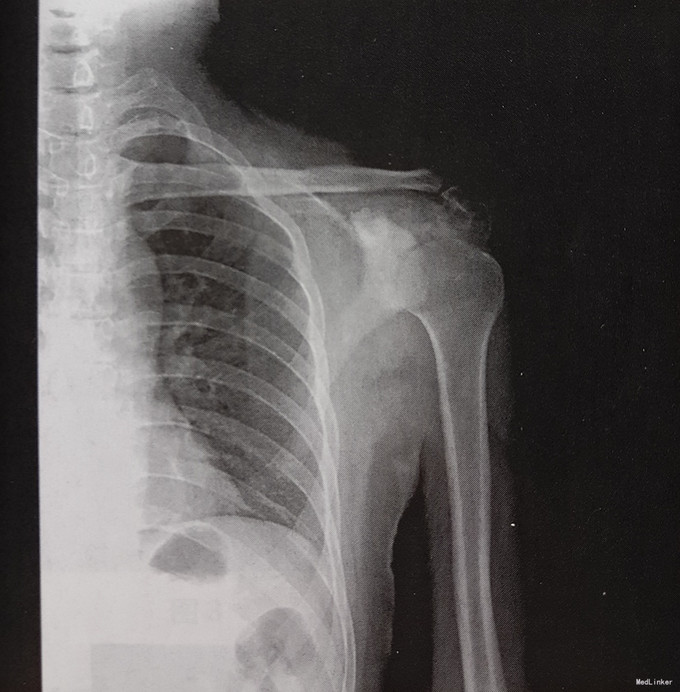

患者男,45岁,右肩疼痛3个月,无外伤及发烧史。患者3月前无明显诱因出现右肩疼痛,疼痛叫剧烈,服用药物及理疗不能缓解,休息时疼痛无明显减轻,为求诊治先来我院。

查体示局部压痛,皮温稍高,不红。生命体征平稳,心肺腹无明显异常。 实验室检查:AKP 180U/L 影像学检查如下

诊断:右肩胛骨占位 治疗:手术治疗 病理:可见形态、大小一致的瘤细胞,诊断为尤文肉瘤。

本例为发生于肩胛骨的尤文肉瘤,X线表现为局部骨质结构模糊,反应性增生,密度增高,具有部分扁骨尤文肉瘤的特点,但发病年龄不典型,诊断有一定困难,鉴别诊断需要考虑软骨肉瘤和成骨转移。成人不规则骨发生的恶性病变最常见的为软骨肉瘤,病灶内出现环形的软骨钙化是诊断最重要的线索。